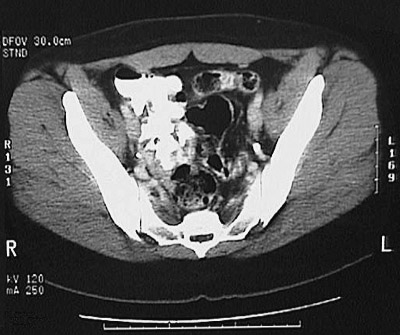

[S2] This is a normal abdominal CT scan with contrast demonstrating the lower abdomen with the sigmoid colon and rectus abdominis muscle and iliacus muscle and gluteus minimus muscle and gluteus medius muscle and gluteus maximus muscle and ilium and sacrum and sacroiliac joint .